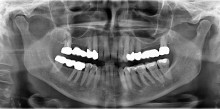

In diesem Beitrag werden die Relevanz und Erkenntnisse klinisch etablierter sowie experimenteller Möglichkeiten der Bildgebung für die zahlreichen Variationen...

In diesem Beitrag werden die Relevanz und Erkenntnisse klinisch etablierter sowie experimenteller...

Eine aktuelle Studie aus Nepal untersucht den „Butterfly Effect“ in unteren ersten Prämolaren und gibt Hinweise auf geschlechtsspezifische Unterschiede.

Eine aktuelle Studie aus Nepal untersucht den „Butterfly Effect“ in unteren ersten Prämolaren...